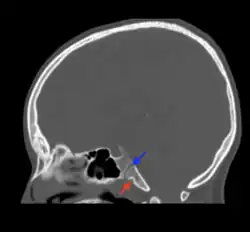

Fossa navicularis magna (also known as pharyngeal fossa or phyaryngeal fovela) is a variant bony depression found at the midline of the occipital part of clivus. This fossa was first described by Tourtual.[1] Its prevalence ranges from 0.9 to 5.3%.[2]

Fossa navicularis magna is located on the anterior surface or pharyngeal surface of the clivus. Its position when present is between the spheno-occipital synchondrosis and the foramen magnum. Size of this fossa varies considerably and its depth ranges from 3.49 to 4.94 mm.[3] A histological study reported the presence of loose connective tissue containing collagen and elastic fibers within the fossa navicularis magna.[4]